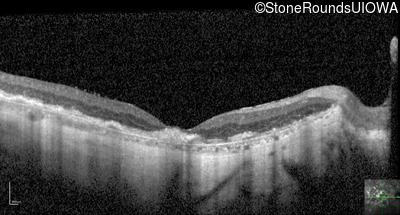

Optical Coherence Tomography - Right - 20/200 +2

Exemplar / OCT Stack

OCT Stack